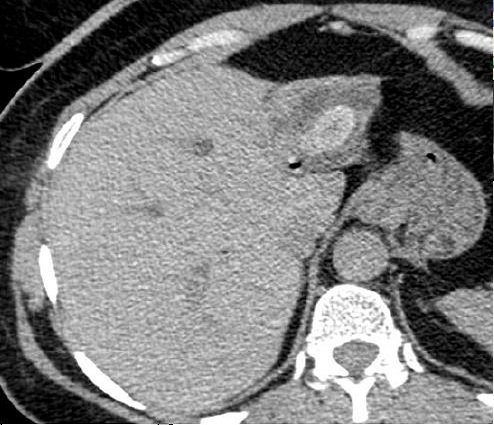

Aspect radiologique d'une

calcul choledocienne .Image de cible du calcul avec

central hyperdensite et a contour de faible de

densite . Image TDM en coupe axiale |

|

Aspect de cible d'une calcul

choledocienne ( fleche rouge ) . Portion dilate en

amont du canal choledoque peut envoyant bien sur ce

coupe . |